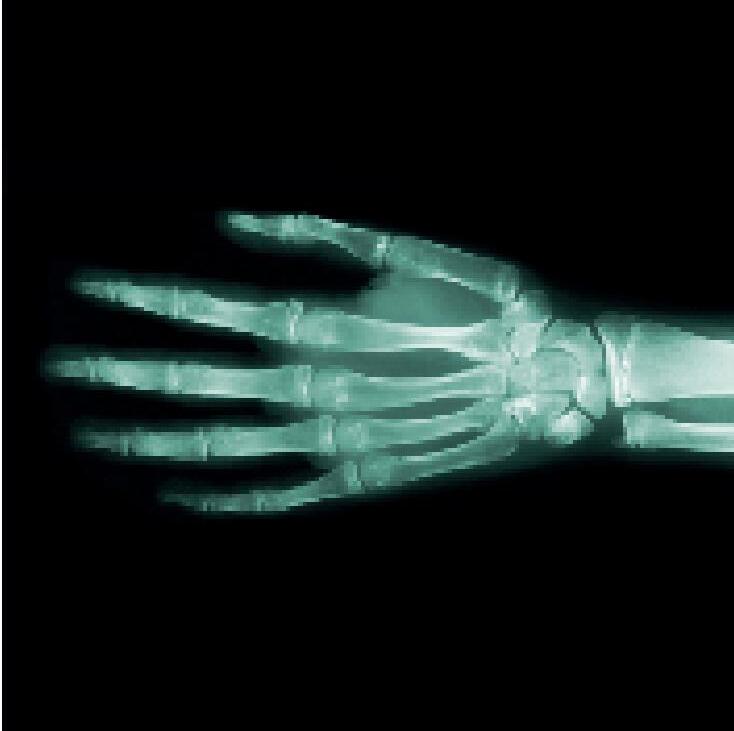

Rentgen

Rentgenové paprsky jsou stejně jako světlo druhem elektromagnetického záření, ale naše oči ho nevidí. Po průchodu tělem jsou zachycovány speciálními kamerami a vytvářejí obrazy kostí.